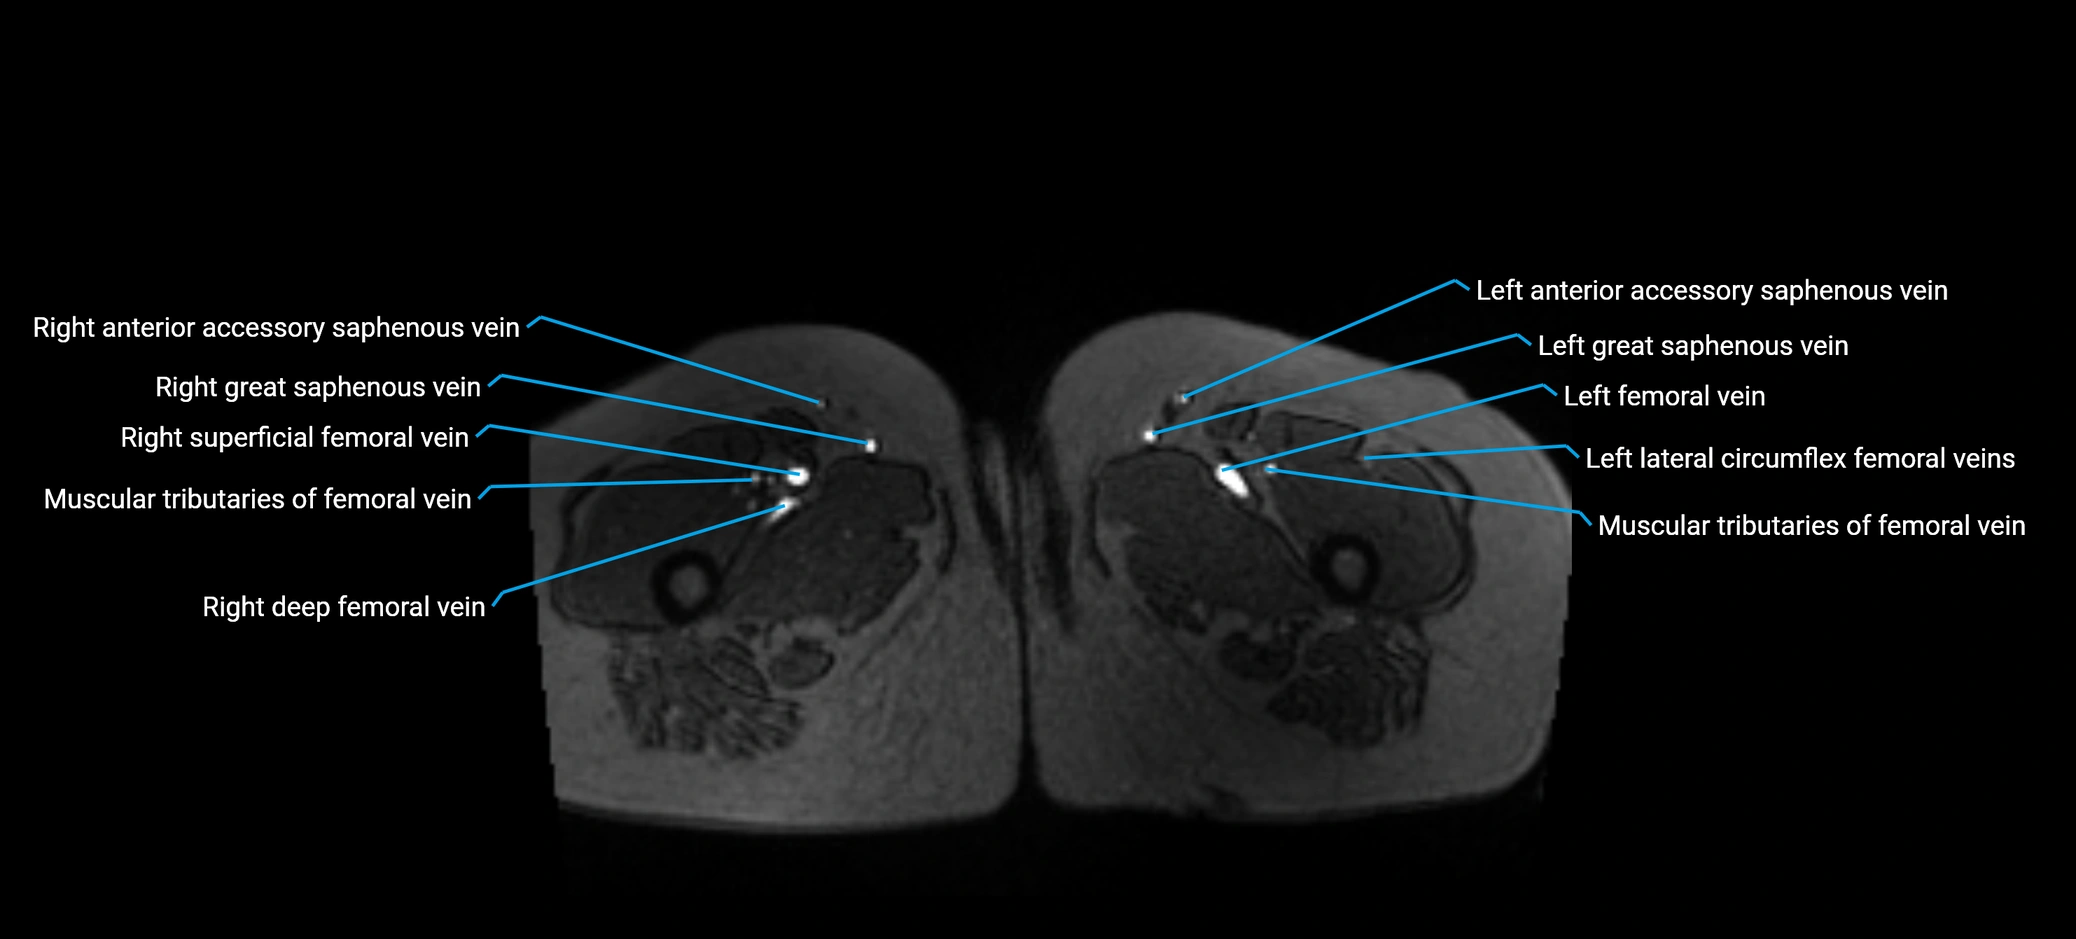

MRI image

image